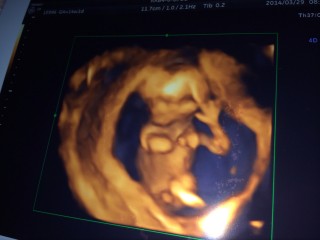

指をおしゃぶり中♪まだ性別はわかりません。胎盤が少しわかるようになってきたと先生が。今の所順調です。

今日ゎ初めての経腹エコーでした。 経腹エコーって事で、午前中仕事休んで旦那サマも一緒に来てくれたのぉ♪♪ いつもゎ動いてくれないんだけど、、、パパもいたからか、おしゃぶりしたり、可愛らしい動きいっぱいしてくれました(´艸`) 順調に成長してて一安心!!!!!! あ~早く性別知りたいなぁぁフフフ